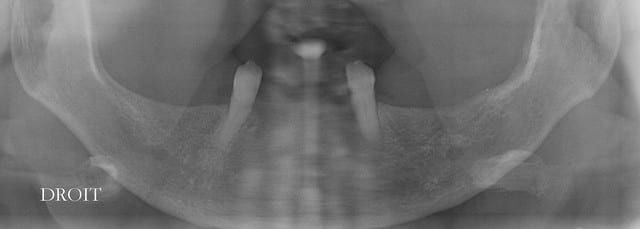

Pour ce cas j’ai effectivement quelques radios.

mais sur cet ordi je ne peux te passer que les panos

Copie de vi p01.07 - Eugenol

Copie de vip  050220081 givypi - Eugenol

Merci pour les radios.

Tu as placé quoi dans l'autre secteur (En bas à droite ?)

L'angulation de l'implant antérieur semble un peu...

trop angulé ?